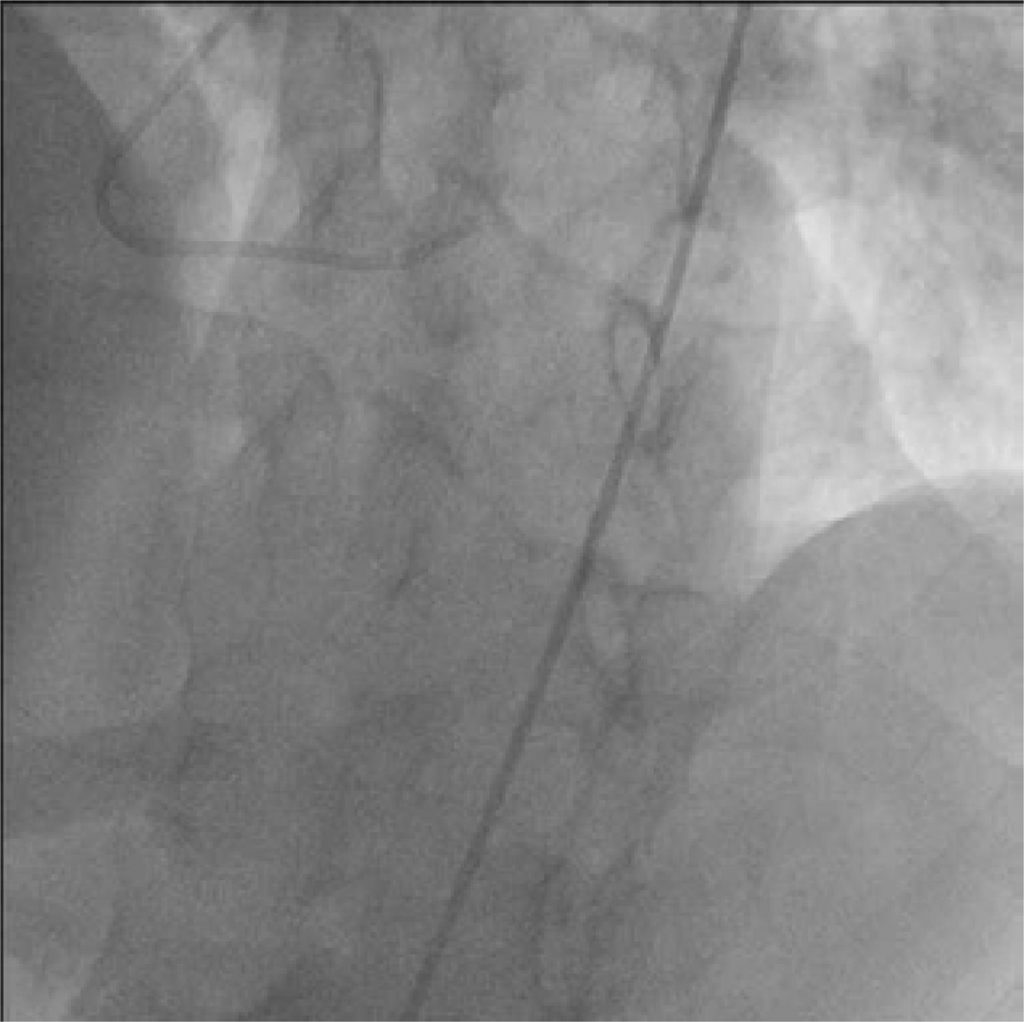

Vídeo 3

Injeção de contraste na artéria coronária esquerda mostra enchimento retrógrado da artéria coronária direita e seus ramos, com padrão de fluxo bidirecional.